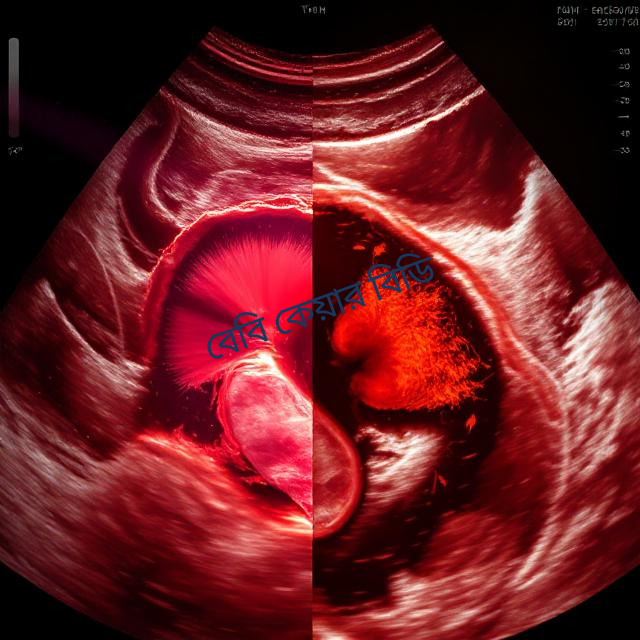

endometrium in ultrasound scan